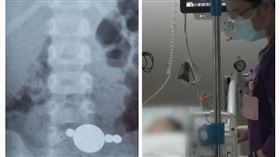

他誤吞手機苦忍半年 原因讓醫傻眼了

埃及一名男子腹痛難忍前往醫院檢查,沒想到醫師透過X光...

2021/10/19 15:15